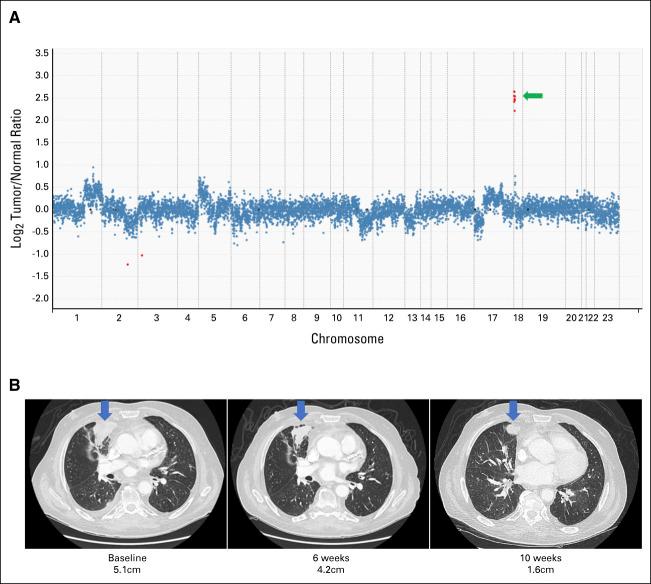

RESULTS

We report response to SRC family kinase (SFK) inhibition in a patient whose lung cancer exhibited amplification, without any well-established primary driver alteration, suggesting that amplification can also function as a primary oncogenic driver. To investigate the possibility of as a primary driver in tumorigenesis, we established preclinical models of YES1 overexpression using human bronchial epithelial cells and normal human breast epithelial cells. We showed that YES1 overexpression conferred sensitivity to SFK TKIs and promoted EGF-independent growth in a YAP1-dependent manner. Analysis of clinical genomic sequencing data from cases of AR to EGFR and ALK inhibitors revealed acquired amplification of in four cases. -mutant and fusion-positive cells overexpressing YES1 or YAP1 were resistant to EGFR and ALK TKIs, respectively, but were sensitive to dual inhibition of the primary driver and YES1.

我们报告了一位肺癌患者对 SRC 家族激酶(SFK)抑制剂有反应,而没有任何明确的主要驱动改变,这表明 扩增也可以作为一种主要的致癌驱动因素。为了研究 是否可以作为肿瘤发生的主要驱动因素,我们使用人支气管上皮细胞和正常人类乳腺上皮细胞建立了 YES1 过表达的临床前模型。我们表明,YES1 过表达赋予了 SFK TKI 的敏感性,并以 YAP1 依赖的方式促进了 EGF 非依赖性生长。对 EGFR 和 ALK 抑制剂 AR 病例的临床基因组测序数据进行分析显示,有 4 例发生了 获得性扩增。过表达 YES1 或 YAP1 的 -突变和 融合阳性细胞对 EGFR 和 ALK TKI 耐药,但对主要驱动和 YES1 的双重抑制敏感。